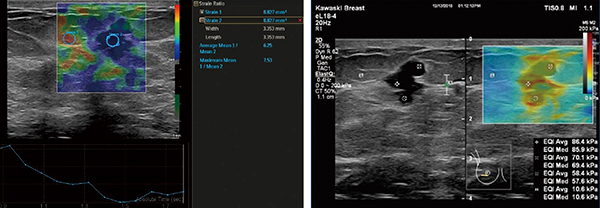

図1 乳腺悪性病変例

ストレイン画像(左)では病変が周囲より青く表示されており,strain ratioは平均6.25,最大7.23で硬い腫瘍として描出されている。シアウェーブ・エラストグラフィ(右)では,腫瘤部が硬く(赤色)表示され,最大88.4kPaと硬い腫瘍であることがわかる。

(画像ご提供:川崎医科大学・中島一毅先生)